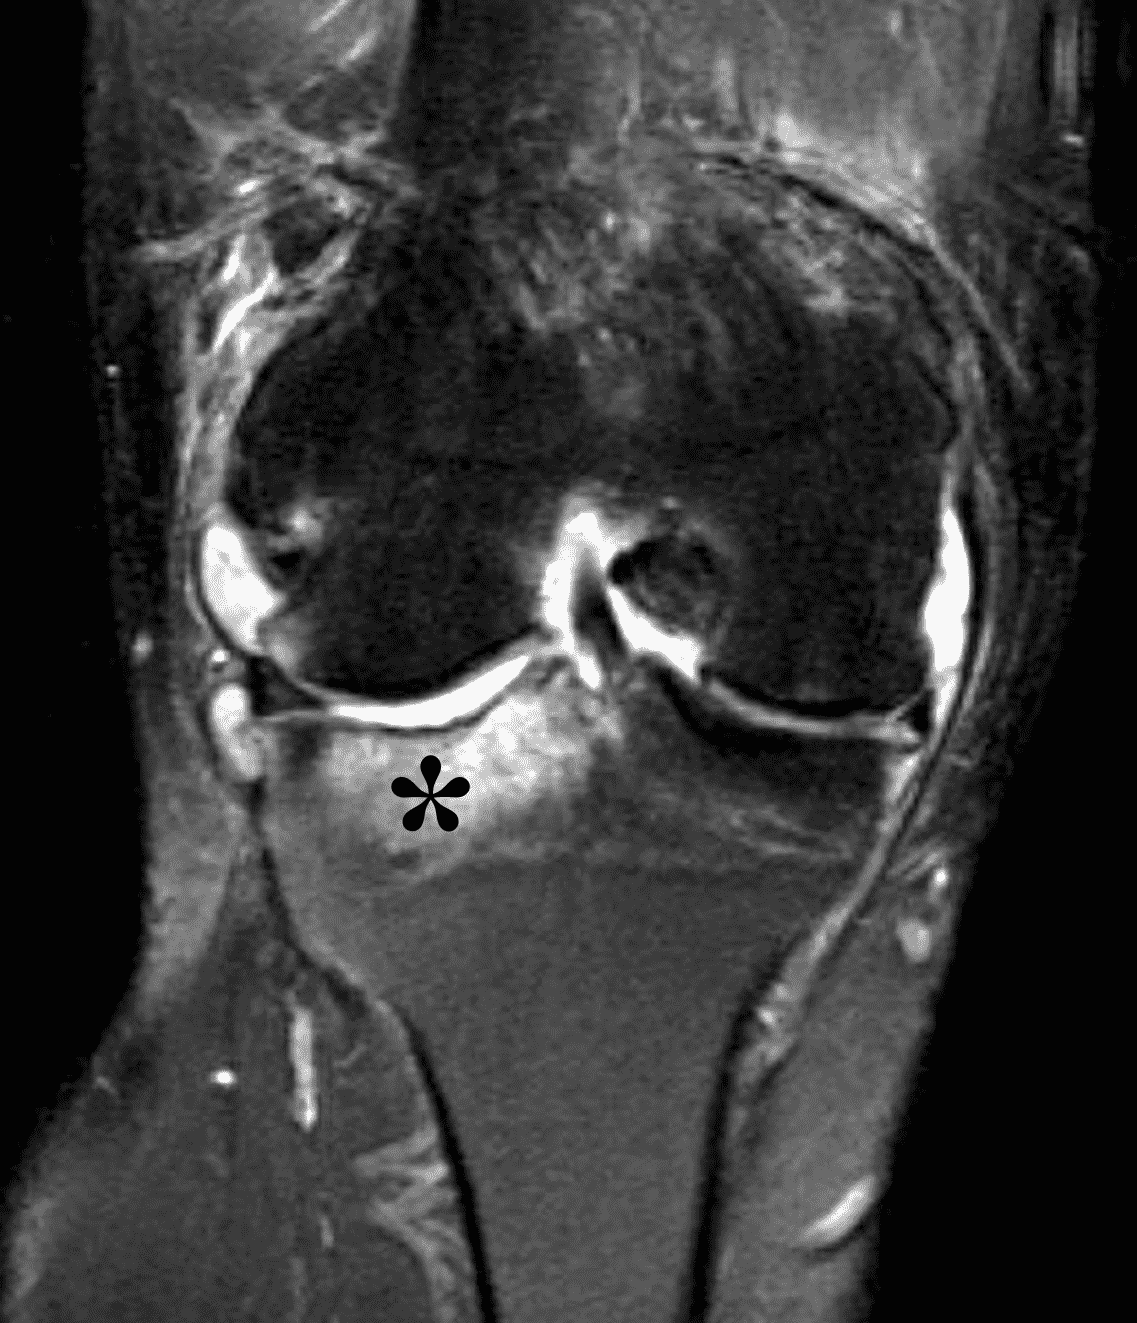

Figure 2: (2A) The coronal image shows a large effusion and severe hypertrophic synovitis (asterisks) in the knee. (2B) On the sagittal image the hypertrophic synovium (asterisks) involves the suprapatellar and infrapatellar recesses as well as the anterior and posterior intercondylar notch. A reactive lymph node (arrow) is present in the popliteal fossa. (2C) The axial image demonstrates myositis (arrows) involving the popliteus and peroneus longus muscles. Note the preserved articular cartilage, lack of erosions, and the absence of subcutaneous or marrow edema.

The causative spirochete invades the synovium, triggering a host inflammatory response that leads to synovial hypertrophy and inflammation, resulting in the characteristic clinical symptoms and imaging findings associated with Lyme arthritis.2 Common MR findings associated with Lyme arthritis include synovitis, joint effusion, popliteal lymphadenopathy, and myositis predominantly involving the popliteus (Figure 4).2,3,9 In contrast to acute septic arthritis due to more common bacteria, subcutaneous edema, marrow edema, erosions, and osteomyelitis are uncommon (Figure 4C).

Figure 4: Lyme arthritis. Fat-suppressed, fluid-sensitive images. (4A) Transverse image shows severe proliferative synovitis in the anterior and posterior joint recesses (arrows). Note the lack of surrounding subcutaneous edema. (4B) In addition to synovitis, the sagittal image shows multiple reactive lymph nodes (red arrows) and popliteal myositis (white arrow). (4C) Coronal image also shows patchy non-joint centered marrow edema in the distal femur and proximal tibia (asterisks), which is uncommon in Lyme disease compared to acute septic arthritis.